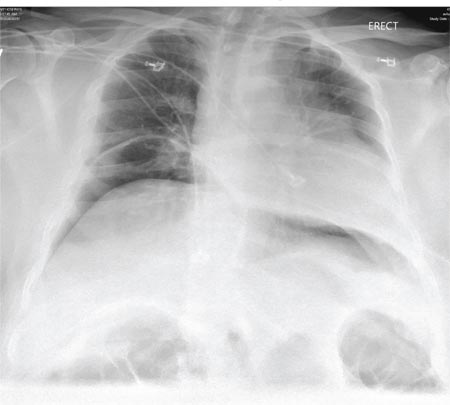

The radiograph demonstrates bilateral elevated diaphragm with a moderate amount of visible free air. With no history of recent abdominal procedures, the primary concern is a perforated viscus.

Urgent surgical consultation, as well as CT of the abdomen and pelvis, was obtained. The imaging confirmed the free air but provided no clear etiology. The patient underwent emergent laparotomy later that day and was found to have a perforated colon.